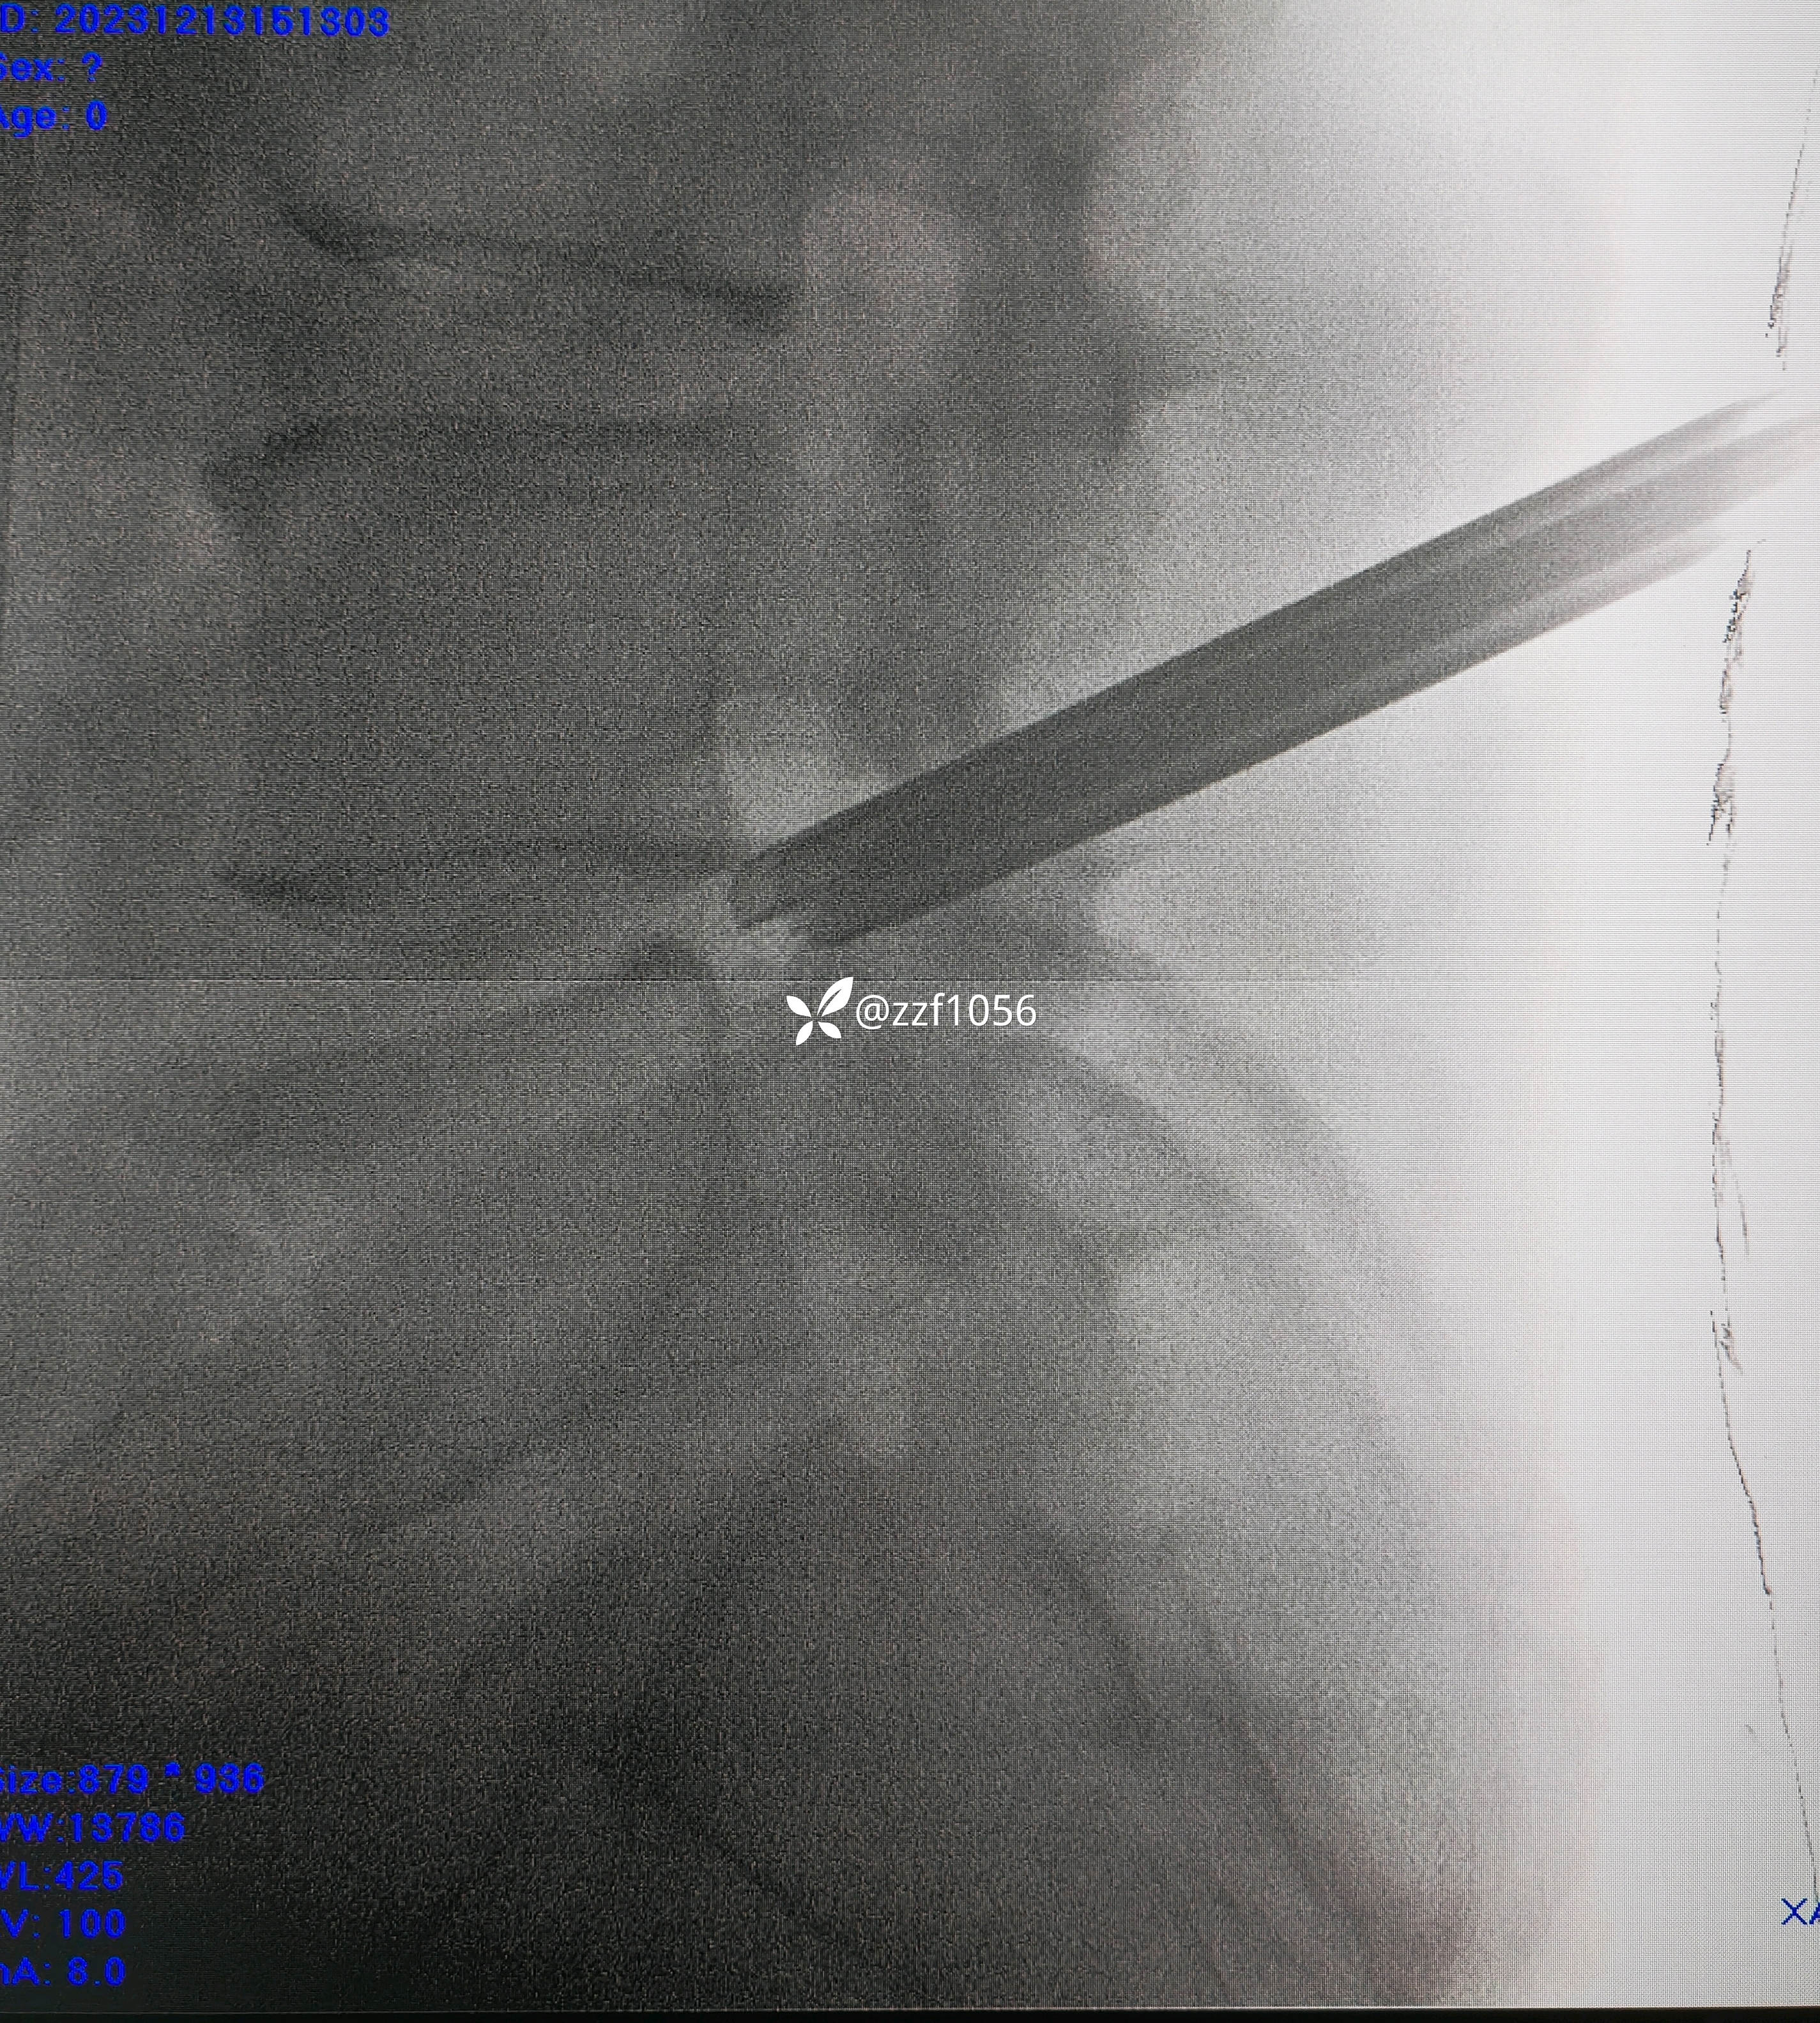

L4/5相对好穿刺

要求椎间孔处的手感

找关节缝的标志